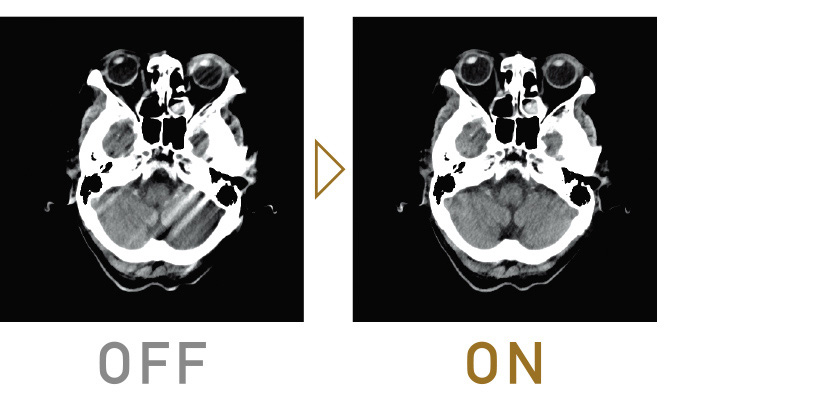

İteratif İşleme, dozun azaltılmasında kullanılır ancak çok fazla hesaplama gerektirir, bu da rutin incelemelerde uygulanmasını zorlaştırır. Supria 128’de, görüntü işleme birimi yenilenip işleme hızı iyileştirilmiştir, böylece rutin incelemelerde İteratif İşleme (Intelli IP) kullanımı kolaylaşmıştır.

Her tesis için optimum ayarlar

Gürültü azaltma gücü, 7 farklı seviyede seçilebilir. Tesisin işletme politikasına göre uygun bir doz ile görüntü gürültüsünü ve artefaktları azaltarak üstün kaliteli görüntüler sağlıyoruz.